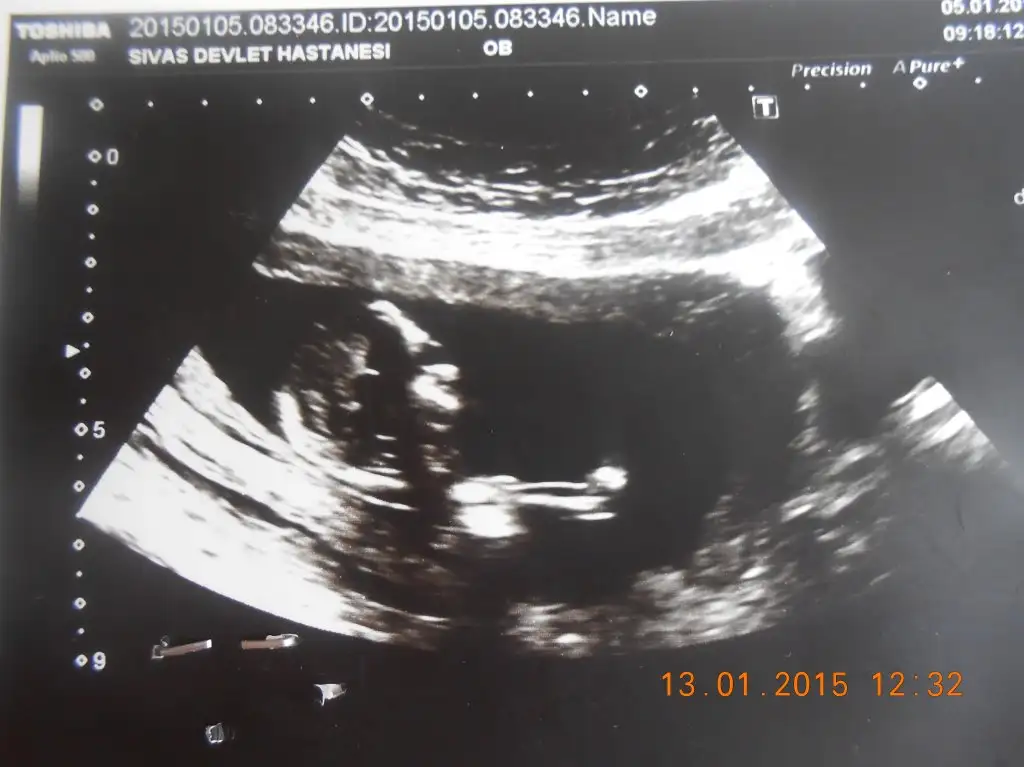

dr soylemeden siz gorun genital nub teorisi ( bebegin cinsiyeti)

Benim bebisin cinsyeti ne olabilir acaba :))

Acaba benim bebegin cinsiyeti nedir sizce arkadaslar bana kiz gibi geldi :))